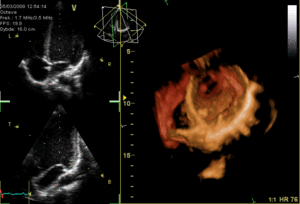

يتم تخطيط صدى القلب عبر المريء عن طريق مسبار يتم إدخاله عن طريق الفم إلى المريء، وذلك للحصول على "نافذة" أفضل موجات فوق صوتية|للموجات فوق الصوتية]] لرؤية الأقسام الخلفية من القلب، إذ أن هذه الجوانب تكون بعيدة عن الصدر، فتكون الصور التي يتم الحصول عليها من الصدر غير واضحة، بينما حينما يتم الفحص من المريء - الذي يُجاور القلب من الخلف مباشرة - أدق للأقسام الخلفية، كما يمكن إنتاج صور ثلاثية الأبعاد[5] لصمامات القلب.

![]() صورة ثلاثية الأبعاد للصمام التاجي. |